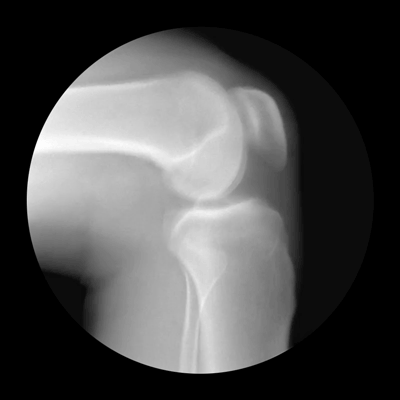

Коленный сустав, с анатомической точки зрения, является самым крупным и имеет сложное строение, поэтому очень часто возникают спортивные травмы и заболевания связанные с повреждением именно этого сустава.

Ежедневно колено подвергается максимальной нагрузке, особенно в процессе силового тренинга или бега, именно поэтому боль в колене возникает довольно часто и в большинстве случаев является следствием начавшейся дегенерации хряща и воспаления.